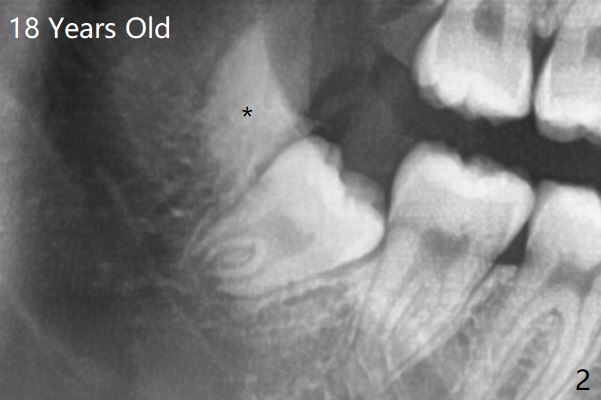

18岁时三角形变大,密度增高(图二)。其实术中发现外斜嵴两侧都不明显(女孩原因?),拔除两侧都需要颊侧去骨。由于左侧智齿颊侧阻生(图三:*),拔除后两侧都放置骨水泥(Bond Apatite,图四:A)促进骨修复,口腔卫生欠缺,可能容易形成牙周炎。